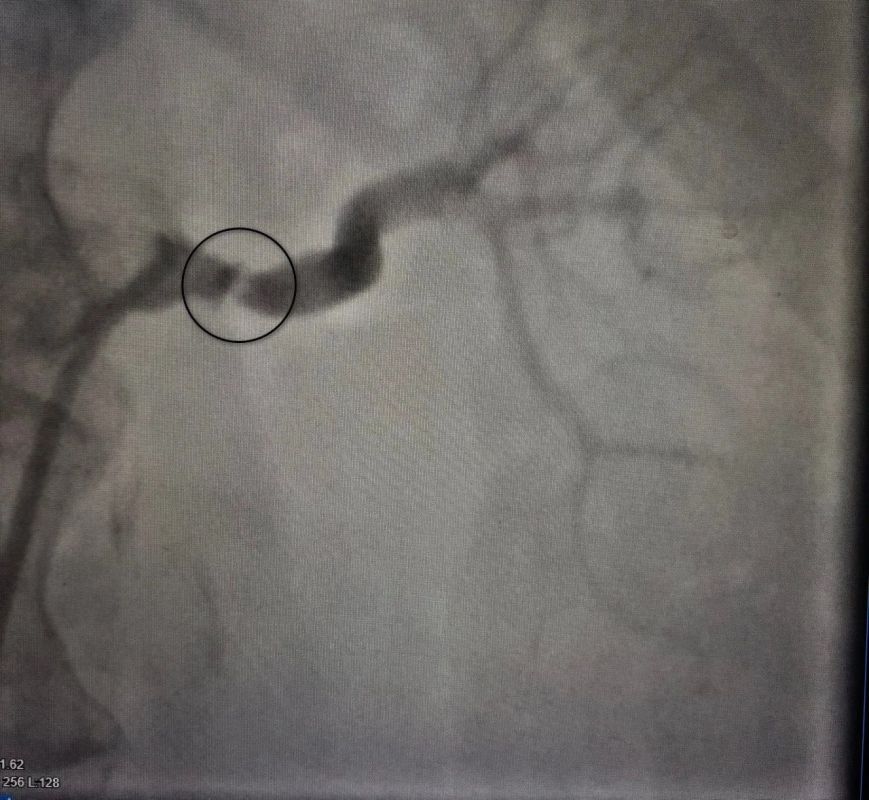

Воронежские врачи успешно диагностировали и вылечили

редкую патологию у 57-летней женщины. У нее была сужена левая почечная артерия,

что привело к тяжелой, невосприимчивой к многокомпонентной медикаментозной

терапии...